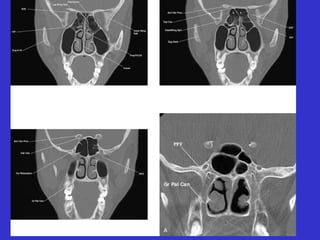

Este documento describe las diferentes proyecciones radiográficas utilizadas para examinar los senos paranasales, incluyendo las proyecciones básicas de Caldwell, Waters lateral y las proyecciones especiales como Hirtz y Waters mentonasal. También describe las diferentes estructuras anatómicas que componen el complejo ostiomeatal anterior y posterior de los senos paranasales.